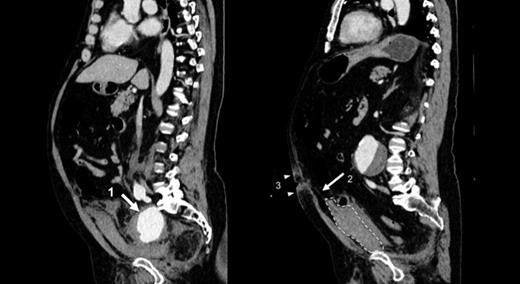

This showed an infrarenal aneurysm of the abdominal aorta measuring 6.5cm and a 6.7cm aneurysm of the right internal iliac artery. Additionally, a mass was also noted arising superiorly from the bladder towards the umbilicus and was reported to be arising from the urachus. (Figure 2)

Sagittal views of CT Abdomen-pelvis showing internal iliac artery aneurysm (Arrow 1) and haematoma formation anterior to the bladder (Enclosed dotted lines) with blood tracking up the lateral umbilical ligament (Arrow 2) towards the umbilicus causing Cullen’s sign (Arrow heads 3).

There was a clear plane between this mass and the rectus muscle. No free fluid was noted in the abdominal cavity.

In this particular instance, the internal iliac aneurysm on the right had ruptured into the retroperitoneum. The blood appears to have tracked up along the obliterated umbilical artery, which is one of the branches of the internal iliac artery. This artery courses as the lateral umbilical ligament in the posterior abdominal wall from the pelvis to the umbilicus. It runs alongside the median umbilical ligament (urachus). Clearly, as shown by the accompanying CT image, the contained rupture had tracked along the lateral umbilical ligament and revealed itself in the form of ecchymosis around the umbilicus.